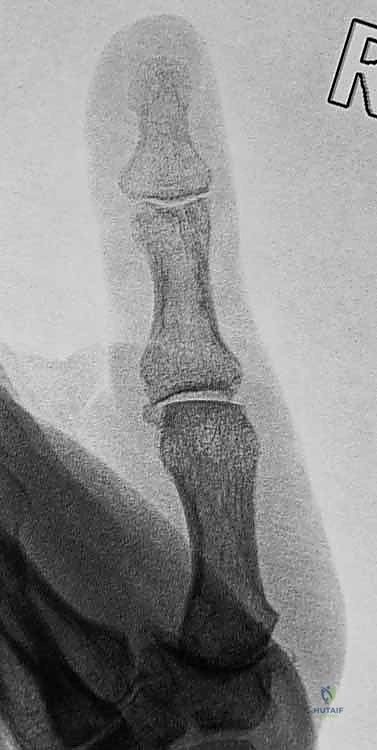

2. التصوير بالأشعة السينية (X-rays)

يُعد التصوير الشعاعي الخطوة الأولى لاستبعاد وجود كسور مصاحبة. في كثير من الأحيان، ينسلخ الرباط ويسحب معه قطعة صغيرة من العظم (Avulsion fracture). كما يتم أخذ صور أشعة تحت الإجهاد (Stress X-rays) لتوثيق عدم الاستقرار.

يحدث الخلع (Dislocation) عندما تخرج الأسطح المفصلية للعظام المكونة للمفصل عن مسارها الطبيعي بشكل كامل بسبب قوة خارجية شديدة. أما الخلع الجزئي (Subluxation) فيعني خروجاً جزئياً مع بقاء بعض التلامس بين العظام.

لفهم طبيعة الخلع وعدم الاستقرار، يجب أولاً أن نغوص في التشريح المعقد لهذا المفصل الحيوي. المفصل السنعي السلامي (Metacarpophalangeal Joint) هو المفصل الذي يربط عظمة المشط الأول (في راحة اليد) بالسلامية الدانية للإبهام (العظمة الأولى في الإصبع).